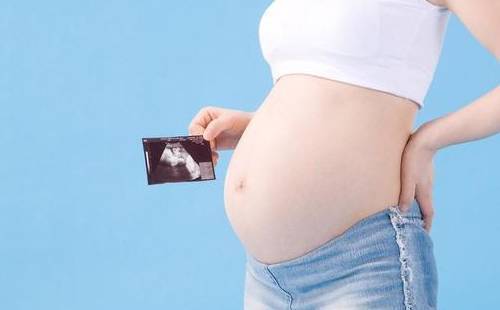

我们可以通过四维彩超,清楚的看到宝宝性别。但是我国的法律明令禁止对胎儿性别进行鉴定,所以医生并不会准确告诉你胎儿性别,但是我们可以通过四维彩超的结果来查看宝宝的性别。

从彩超看生男生女?我国严禁查看胎儿性别,医生通过任何途径向孕妇透露或者暗示胎儿的性将会受到法律的追究。所以在做四维彩超时,医生一般会避开胎儿的下半身,不会在图像上显现出胎儿的生殖器官。而且对于年轻的父母来说,无论男宝宝还是女宝宝都是这个家庭的宝贝,了解胎儿的健康发育情况才是做四维彩超的意义。

第四、从胎儿头脸部看

胎头位于耻骨上,头骨光环光整,脑中线居中,胎儿上唇,鼻骨可预示,生男孩。

47mm,透声性杰出,为男孩。